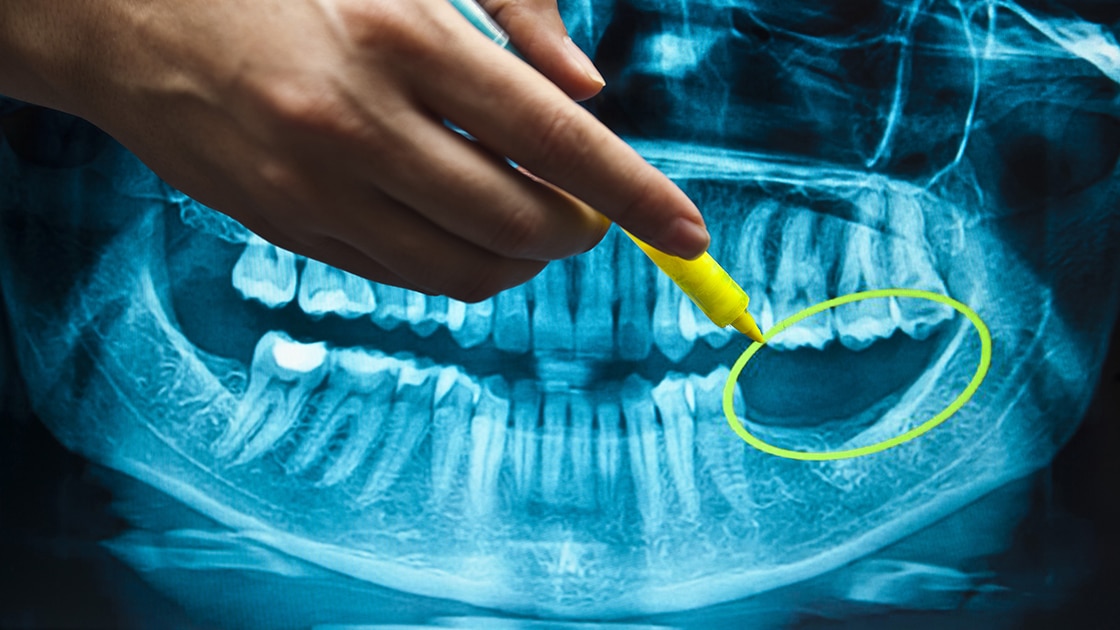

Once a tooth is lost, several things begin to happen that are not immediately noticeable to a patient and can have a significant negative effect on both health and appearance. Tooth roots help hold teeth in place, but they are also critical in maintaining health in the surrounding gums and supporting bone structures. Bone loss in the jawbone is one significant problem that naturally occurs once a tooth is lost. This bone loss can compromise the integrity of neighboring tooth roots and tooth stability, and it is also a large part of what causes the “sunken” look that is seen in people who have lost several or all of their teeth. It is the reason patients who wear dentures find that over time their dentures are harder and harder to fit and keep in place.

Dental implant placement can help generate bone growth in the area around the implant, which not only strengthens the bone and builds support, but can also alleviate the sunken look that can occur with bone loss in the jaw. This process is known as osseointegration and is a significant benefit of implant placement because it can also help prevent future bone loss.